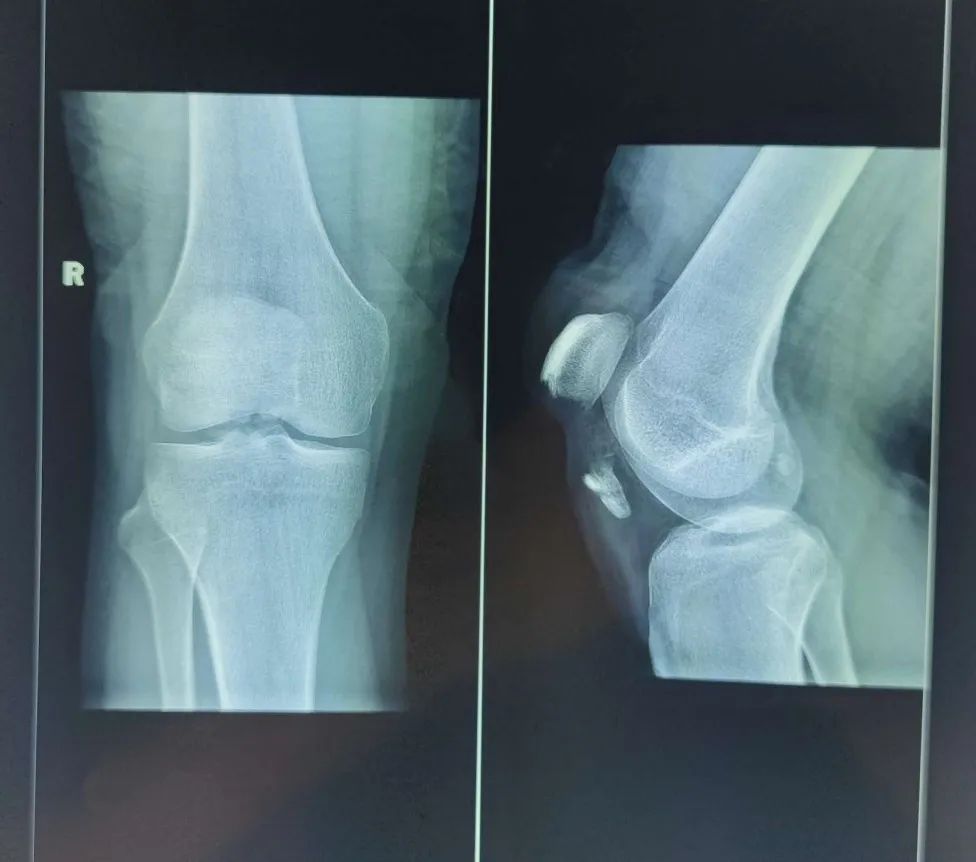

11月14日晚上,家住七雄街道的17岁少年天赐(化名)在骑电动车时不慎摔倒致右膝受伤,随即感到伤处持续性剧烈锐痛,遂来我院就诊。接诊医生经仔细查体并结合X线摄片,诊断天赐为“髌骨骨折”,收住小儿外科病区。入院后,积极完善各项相关检查,进一步CT检查提示:髌骨远端粉碎性骨折。

▲X线摄片显示:髌骨下级撕脱骨折

▲CT检查显示:髌骨远端粉碎性骨折